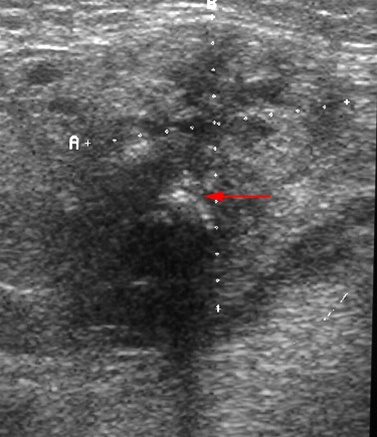

Ultralyd af kroniske betændelsesforandringer i glandula submandibularis (underkæbespytkirtlen) med mikroabscesser og en forkalkning (pil) som giver ekkoskygge.